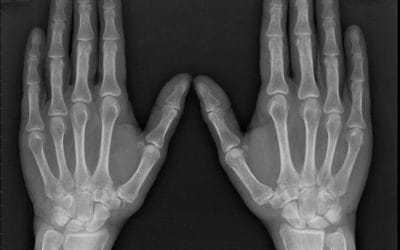

PT in the News: Jane Brody on Arthritis in The New York Times

At BBPT, one of our specialties is orthopedics, in which we treat musculoskeletal conditions like osteoarthritis. Many...